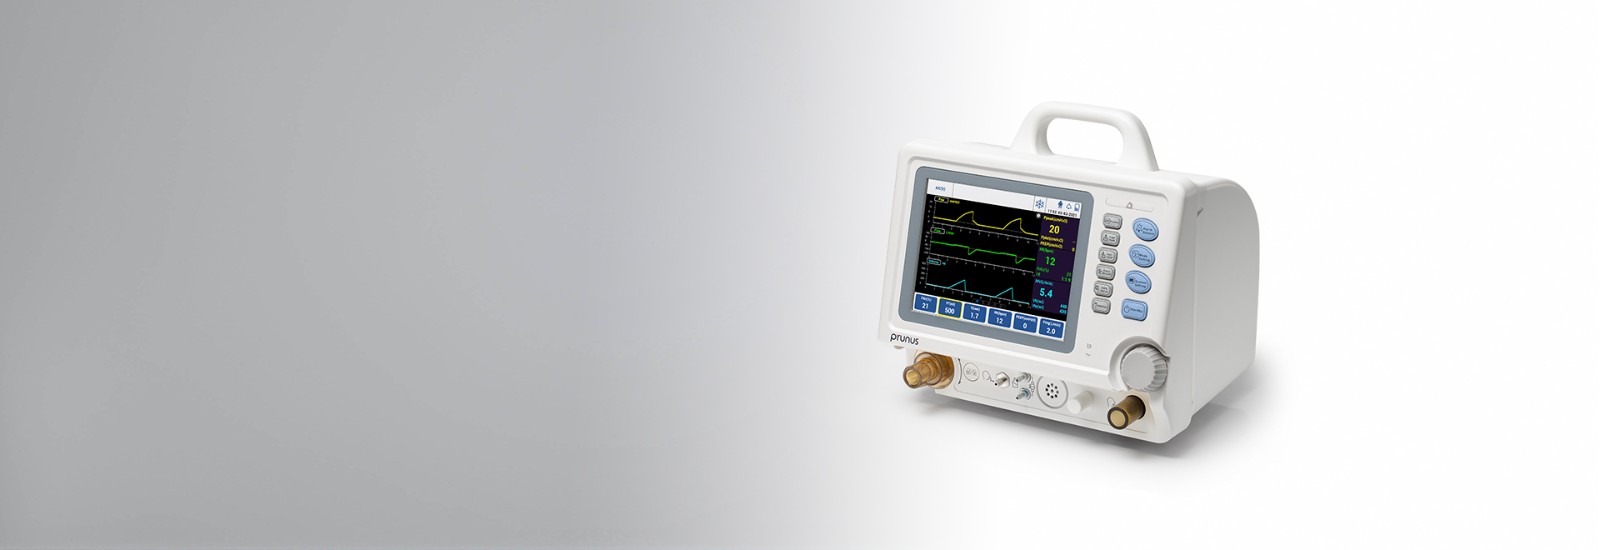

Boaray 2000D est le ventilateur de niveau ICU le plus léger (seulement 7,5 kg) et le plus compact, simple à configurer, facile à utiliser et polyvalent. Les patients pédiatriques et adultes sont disponibles pour tous les niveaux d'acuité aux soins intensifs et aux soins intermédiaires.